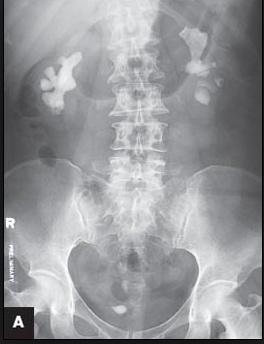

Xray: Cavitary lesion, may look like TB